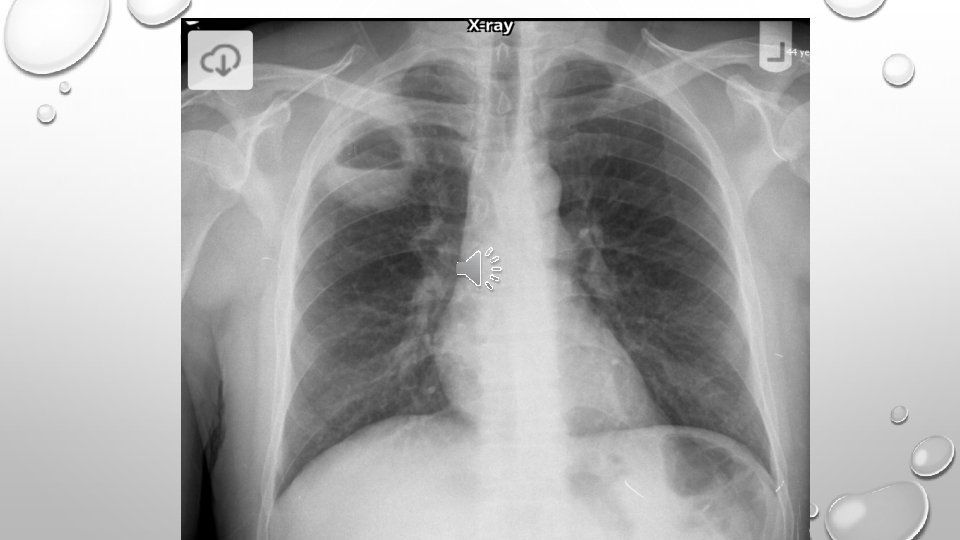

• LUNG ABSCESS REPRESENTS NECROSIS AND CAVITATION OF THE LUNG FOLLOWING MICROBIAL INFECTION • LUNG ABSCESS CAN BE SINGLE OR MULTIPLE

• LOCALIZATION OF INFECTION IN PRIMARY LUNG AB. IS IN POSTERIOR UPPER LOBE AND SUPERIOR LOWER LOBES • RIGHT LUNG IS AFFECTED MORE COMMONLY • MICROBIOLOGY IS POLYMICROBIAL • A PUTRID LUNG AB. REFERS TO CASES WITH FOUL SMELLING BREATH , SPUTUM, OR EMPYEMA

DIAGNOSIS • IMAGING • NEEDLE ASPIRATION